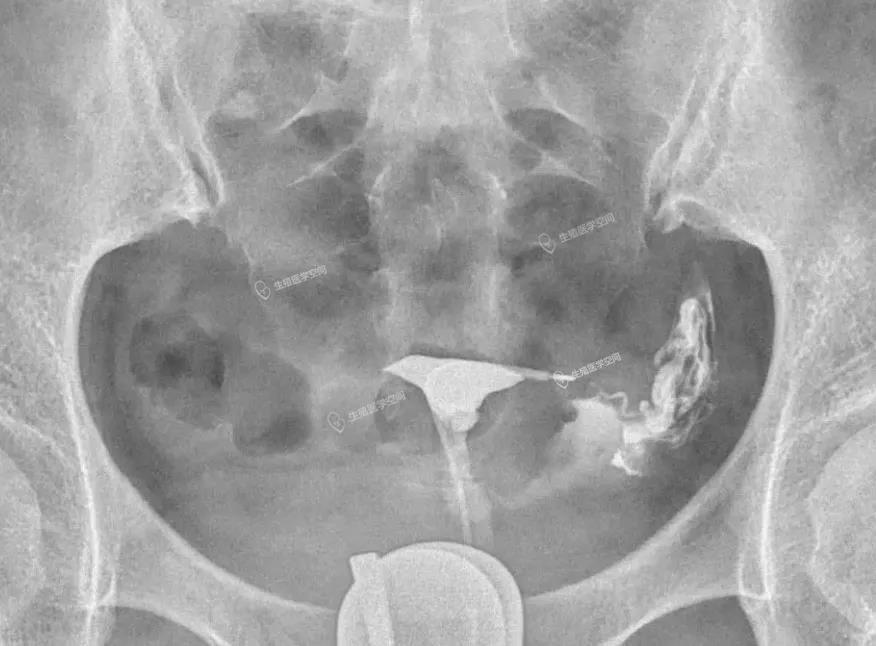

病例1 女 28岁 原发不孕,子宫输卵管造影发现双侧输卵管间质部阻塞,为结核性输卵管闭塞,不管是宫腹腔镜或放射科的介入再通术都疏通不成功。男方检查均正常。于是做试管婴儿。37周多剖宫产一对双胞胎。

病例2 女 32岁 继发不孕,子宫输卵管造影发现双侧输卵管峡部阻塞,为峡部结节性输卵管炎(SIN)所致输卵管闭塞,不管是宫腹腔镜或放射科的介入再通术都疏通不成功。男方检查均正常。于是做试管婴儿。足月顺产一健康婴儿。